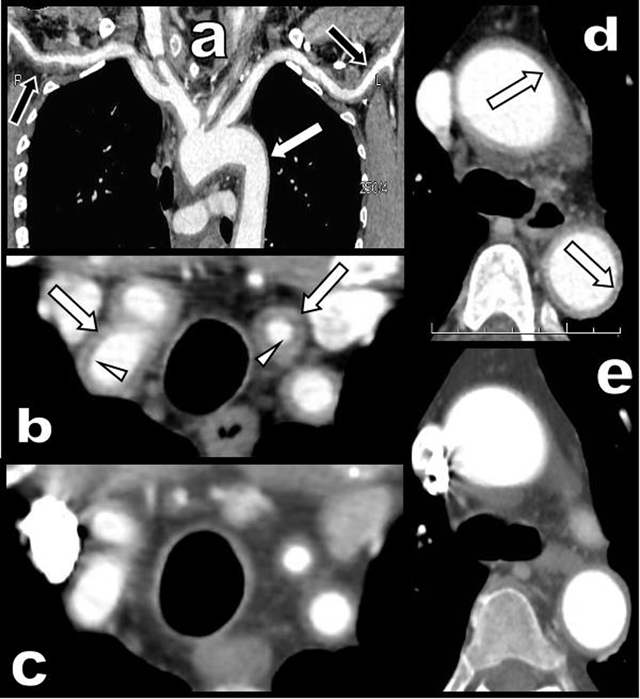

A 65-year-old woman presented with a three-month history of persistent ocular-nasal catarrh, sub-febrile state, myalgia, night sweats, weight loss and early daily bi-temporal pain. Severe biological inflammatory syndrome with CRP at 105 mg/l and sedimentation rate at 97 mm was present. Colour Doppler Ultrasound (CDU) (Figure 1) showed a typical inflammatory “halo sign” (black arrowhead on a) of the temporal arteries. A similar “halo sign” was found along the common carotid (white arrows on c, d, and e) and vertebral arteries (black arrows on d and e). The intima remained visible (white arrowheads on e). Computed Tomography (CT) angiography (Figure 2) showed blur homogeneously enhancing wall thickening of the aortic arch (white arrows on a and d) and of its large emerging arteries (white arrows on b). The axillary arteries were also affected (black arrows on a). Moderate thickening of the abdominal visceral aorta was also found (not illustrated). Hypodensity of the intima contrasted with enhancement of the inflamed media (white arrowheads on b). Temporal artery biopsy (Figure 3a and b) confirmed typical giant cell arteritis (GCA) with involvement of the media (yellow star) and adventice (white star) by chronic lymphocytic inflammation. Reactive intimal hyperplasia (black star) causing luminal collapse (white arrow), characteristic fragmentation of the internal elastic lamina (black arrows) and giant cells (black circles) were also diagnosed. Classical massive corticosteroid treatment was immediately started with rapid clinical and biological improvement. The “halo sign” and diffuse arterial thickening had, drastically, nearly completely resolved on post-therapeutic CDU (Figure 1b and f) and CT (Figure 2c and e) nine months later.

Figure 2

CT angiography of the aortic arch and of its large emerging arteries before (a, b, d) and after treatment (c and e).